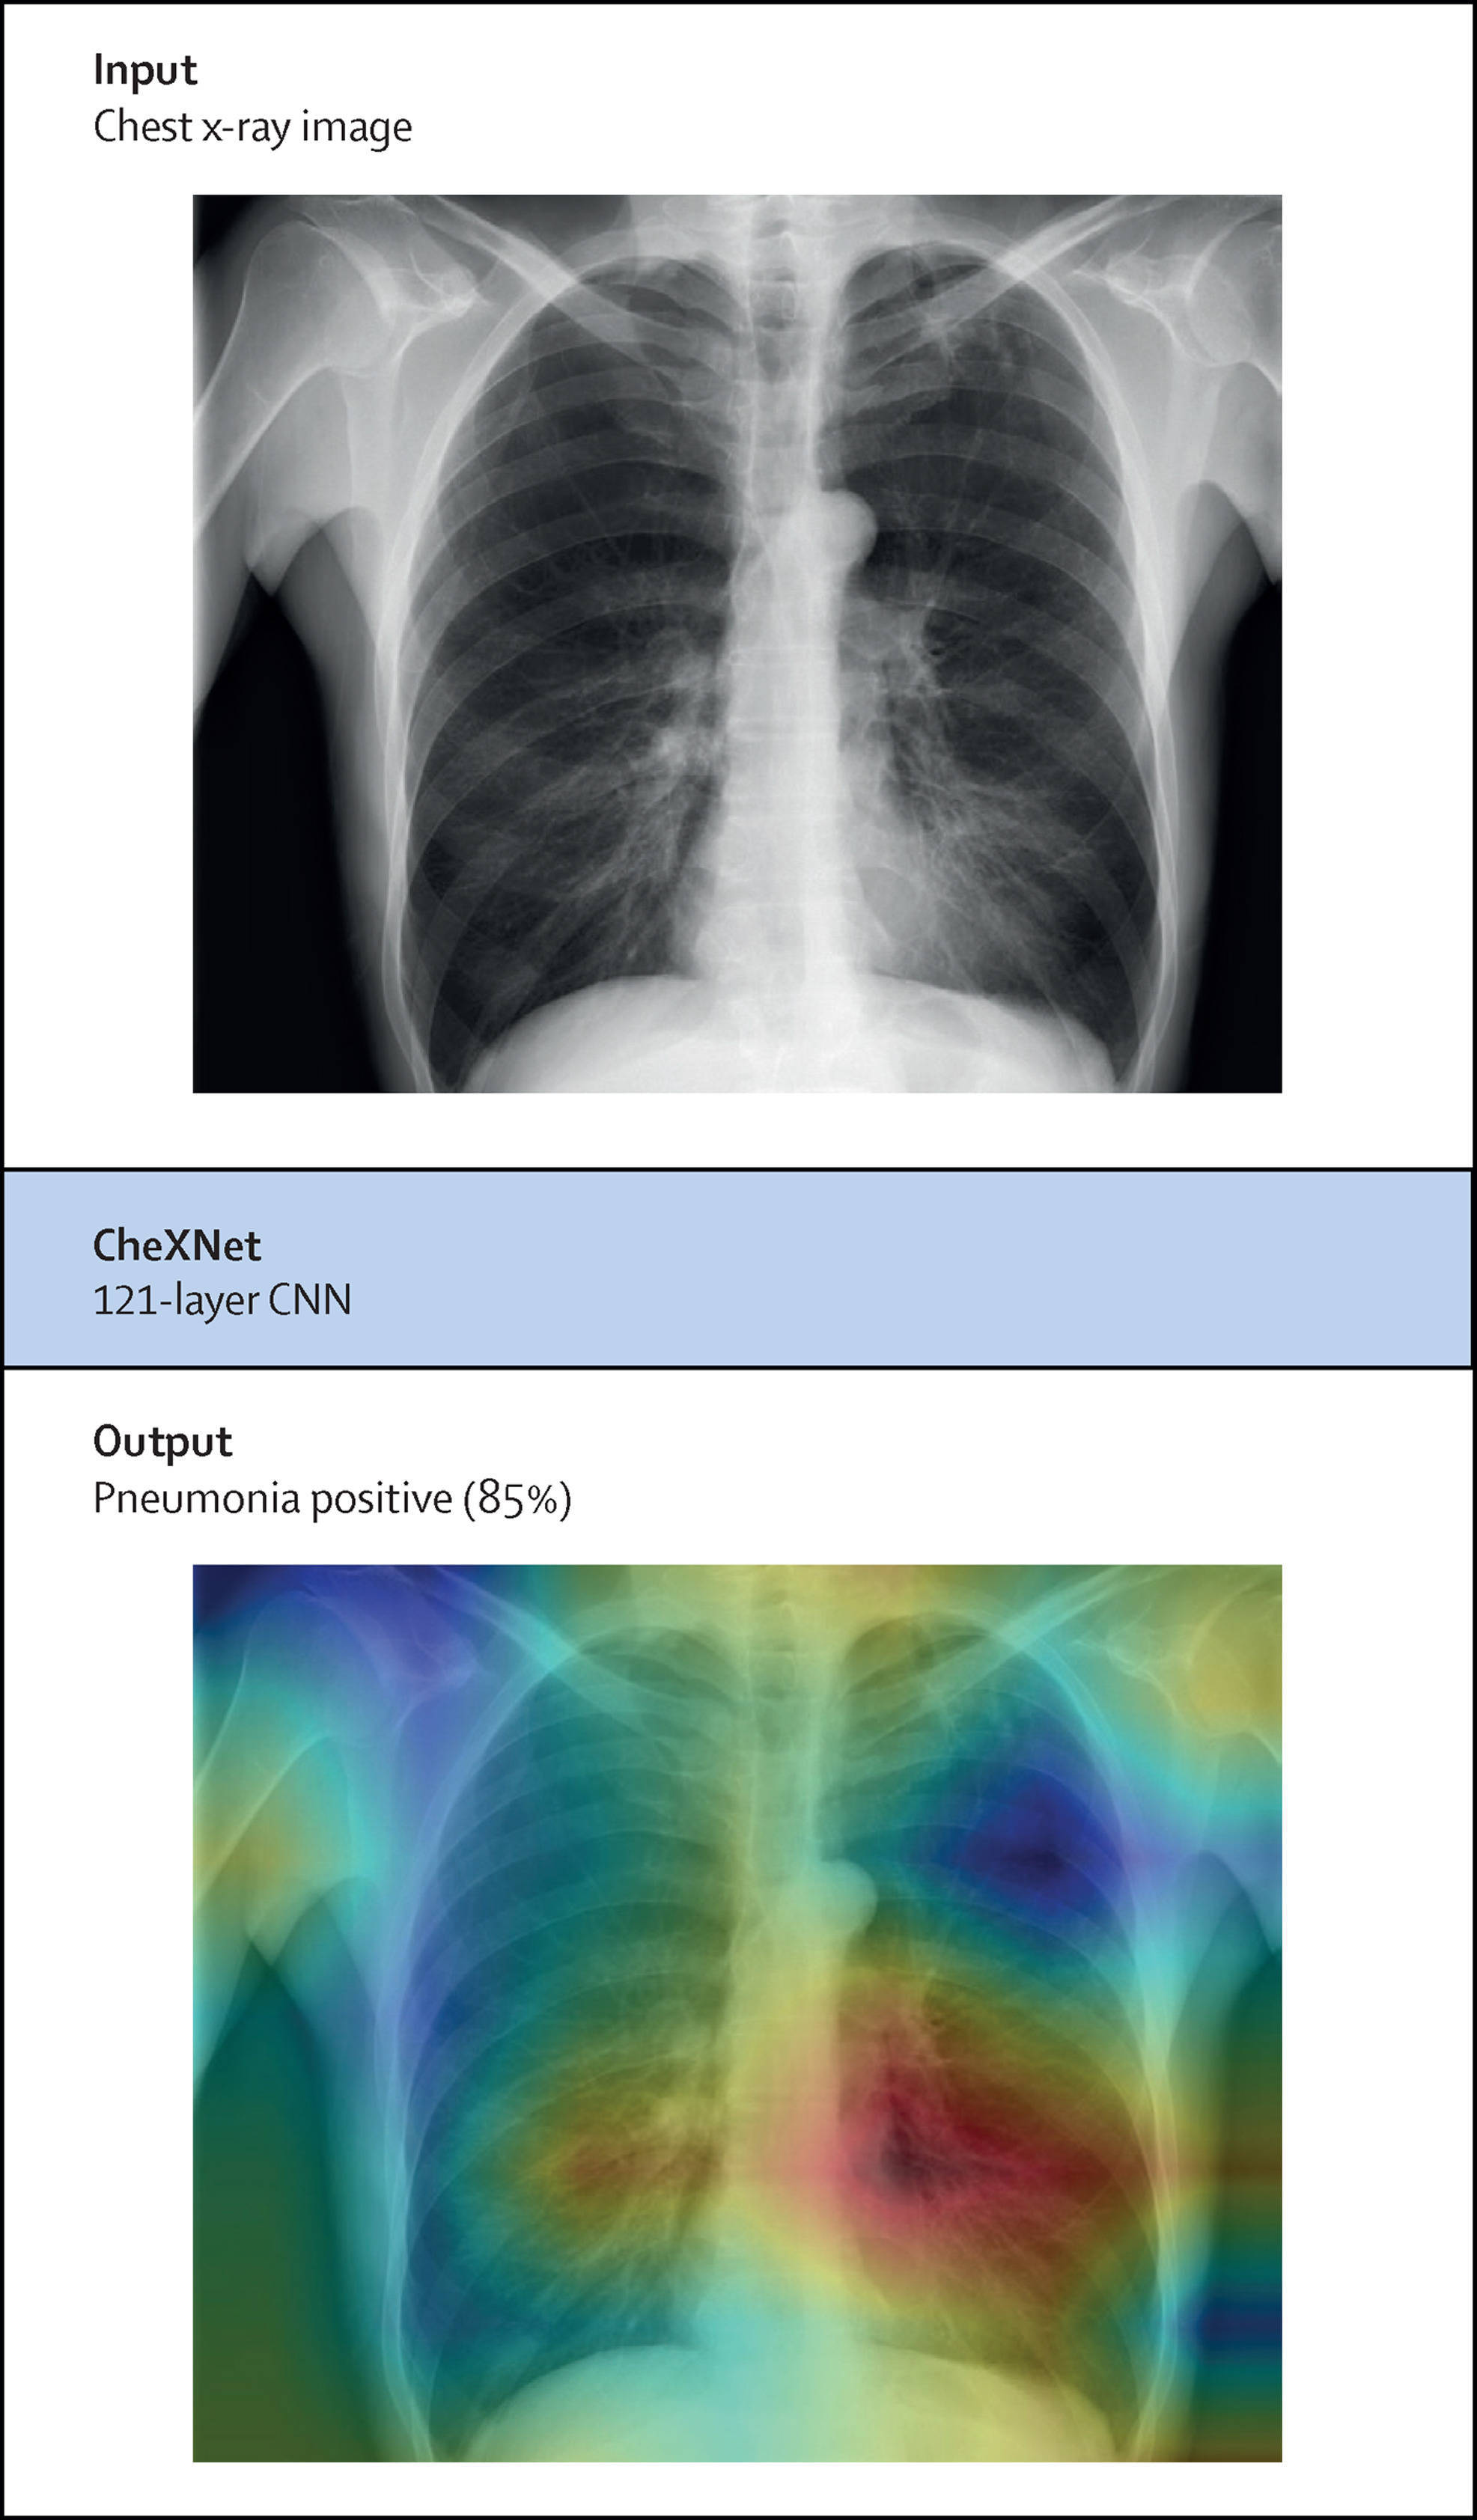

事后可解释性思路是通过各种途径剖析其决策过程 。 一种流行的事后可解释性形式称为热图 , 热图突出图像的每个区域对给定决策的贡献程度 , 并且具有说明性 , 常用在医学成像模型中 。

图说:用于检测胸部X光肺炎的深度学习模型的事后解释方法生成的热图

(根据深度神经网络 , 较亮的红色表示重要性级别较高的区域 , 较深的蓝色表示重要性级别较低的区域)

但Ghassemi等研究发现 , 本应解释为什么AI将患者归类为肺炎的热图 , 即使是图中“最热区域”(最影响判断区域)也包含着在医生看来有用和无用的信息 , 简单地定位该区域并不能准确揭示模型认为有用区域的确切内容 。